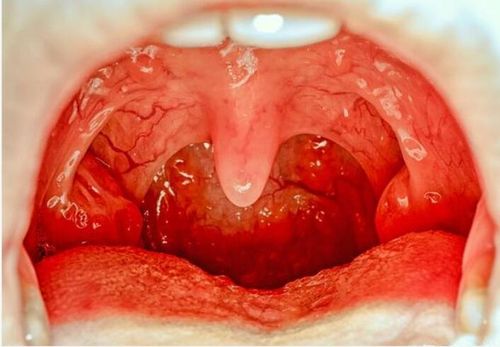

急性咽炎图片高清图片

急性咽炎图片高清图片,急性咽炎的症状图片

急性咽炎的症状图片

急性咽炎真实图片

急性咽炎口腔图片

急性咽炎的图片

急性咽炎图片